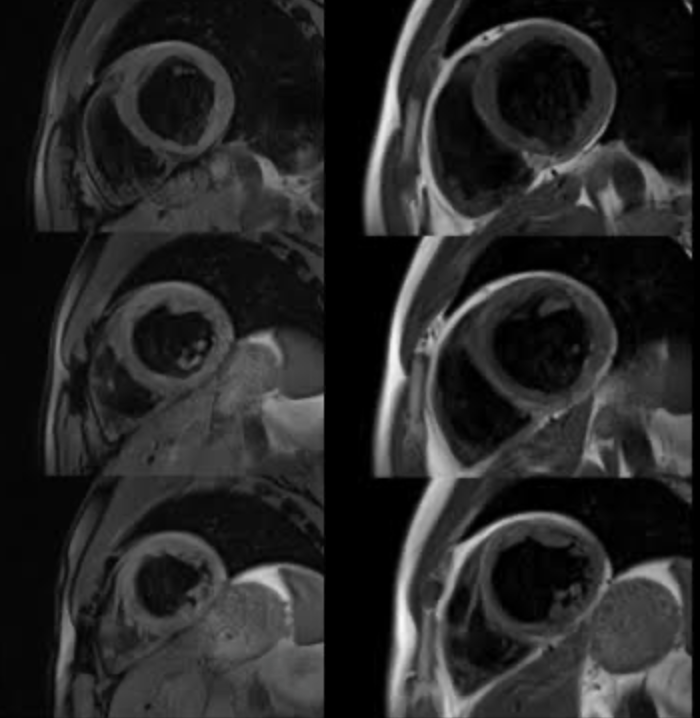

Figure 3. Short-axis LGE images demonstrating circumferential/ring-like late gadolinium enhancement in the left ventricular myocardium